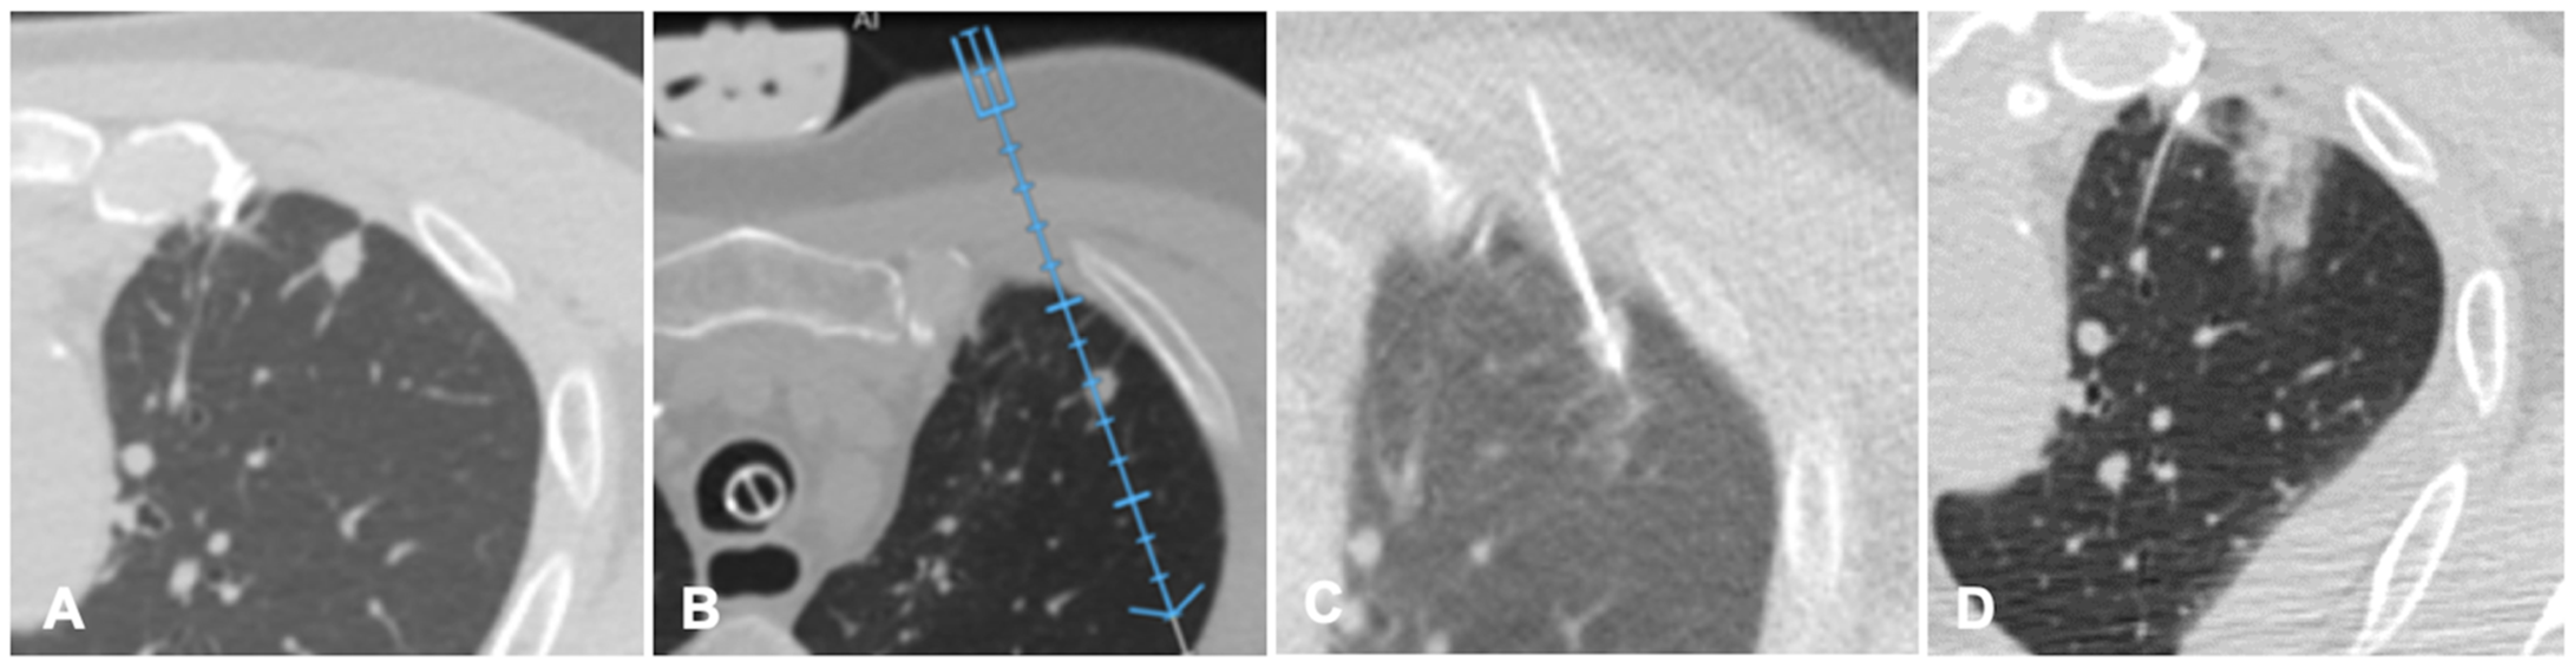

Figure 4. Case of an oligometastatic colonic adenocarcinoma in a patient with a nodule in the upper lobe of the left lung treated with microwave ablation (MWA). (A) Axial view of the preoperative Computed Tomography (CT) scan confirms the presence of a 4 mm nodule in the left upper lobe adjacent to the pleural profile. (B) Using electromagnetic virtual navigation guidance, the skin entry point is selected and the MWA antenna is inserted. (C) Multiplanar reconstruction of intraoperative CT scan along the needle long axis showing correct targeting of the lesion. (D) Control CT at the end of MWA treatment showing complete ablation without complications.

FI technique is recently being applied to lung procedures since software algorithms were developed to register the intraprocedural anatomic imaging with preprocedural PET/CT data. Some studies reported the experience of fusion PET/CT-CBCT studying it in guiding percutaneous biopsy of lung lesions compared with CBCT guidance [40,41,42]. PET/CT-CBCT-guided is feasible and safe as CBCT-guided biopsy with a lower number of non-diagnostic samples and false-negative cases, with evidence of metabolic information provided by a prior PET/CT and a better quality of the samples obtained with FI guidance [40]. Systems that allow to guide a virtual needle on a pre-acquired lung CT have been implemented to reduce the number of CT acquisition required in lung procedures and to improve the non-axial approach in CT guided lung ablations. A case of a lung nodule treated with microwave ablation is shown in Figure 4.